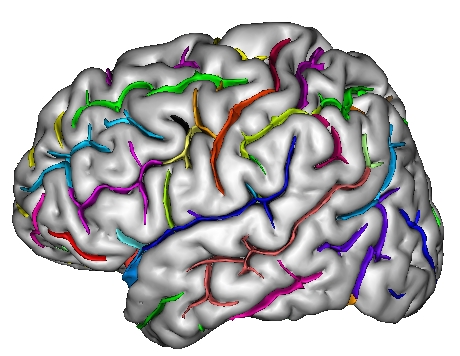

Each fold includes several buckets of voxels corresponding to the topologically simple surface making up its core (GREEN), its bottom lines (including branche's bottoms) (RED) and a few additional voxels corresponding to small or spurious branches (CYAN). Here is the example of a central sulcus:

You can get images of the bottom, of the simple surface or the sum of everything. You can also get the junction between each sulcus and the brain hull, which corresponds to the line which is sometimes drawn manually by some teams. Anatomist's viewer show you the result (the eyes):